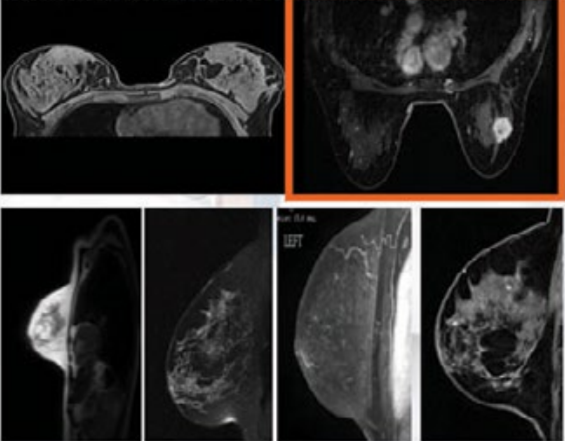

U.S. TCIA database. Breast Cancer Image Data (BRCA) Data showed 230,167 images of 139 patients (for use). MRI, General Breast Cancer (MG) tests (88.58GB) that have already been performed. Breast cancer MRI images show a variety of different pictures. This analysis shows the complexity of the analysis. Categorized by boxes in [Figure 1] to reduce (complexity) I decided that I would use the images with tumors. 49 different patients with a total of 747 images were selected to collect the data.